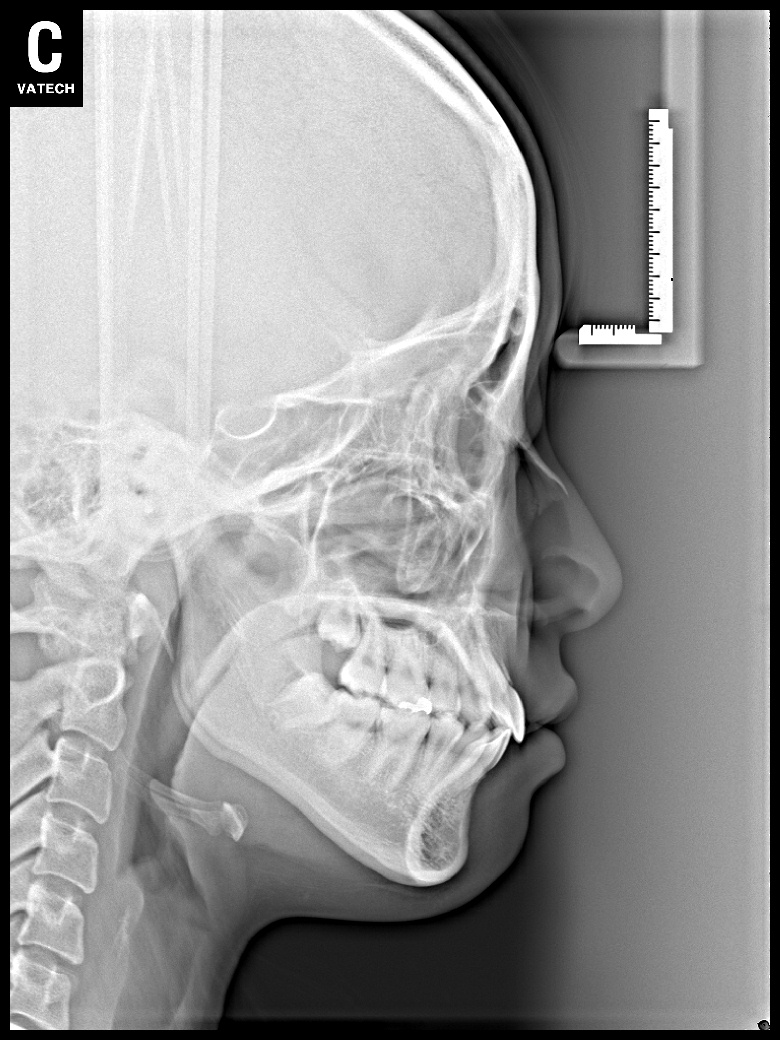

치료 전 사진입니다.